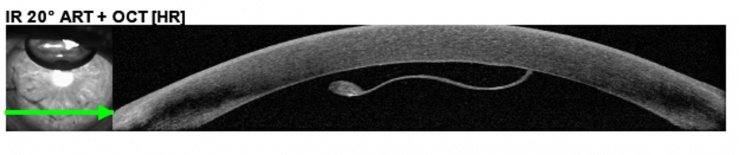

Fig 1. DMEK graft with detached peripheral edge